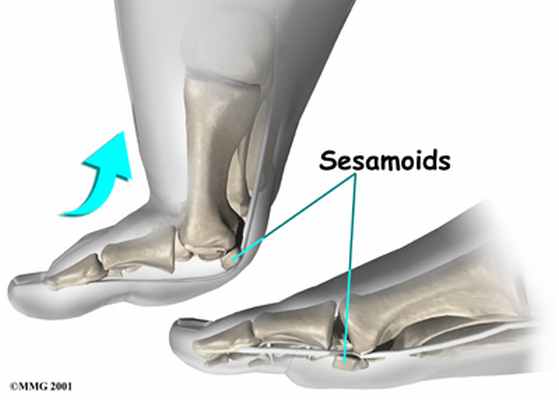

— Os hallux — две постоянные сесамовидные кости в области соединения первой плюсневой кости с первым пальцем (внутри сухожилия короткого сгибателя большого пальца стопы). Они увеличивают рычаги воздействия сухожилий сгибателей на фаланги первого пальца, а также снижают силу трения сухожилий о мягкие ткани в положении разгибания первого пальца.

На стопе под 1 плюснефаланговым суставом имеются две сеcамовидные кости. Каждая кость может состоять из двух долей, которые отделены друг от друга, что считается вариантом нормы. Сесамовидные кости представляют собой опору для сухожилий сгибателей большого пальца. Сесамовидные кости своей массой увеличивают расстояние от сухожилия до центра вращения 1 плюсне-фалангового сустава. Происходит увеличение рычага силы сгибания пальца и увеличение момента мышц, которые сгибают большой палец, что необходимо для отталкивания от опоры.

В обуви на каблуке стопа находится в вынужденном эквинусном положении. Эквинусная стопа обладает сниженной возможностью к распределению нагрузки по своей поверхности. В эквинусной стопе происходит перераспределение нагрузки по сравнению с босой ногой и ногой в обуви на низком каблуке. Нагрузка смещается по стопе в область 1 луча, где расположены самые мощные опорные структуры переднего отдела стопы и вызывает реакцию со стороны большого пальца и 1 плюснефалангового сустава и сесамовидных костей.